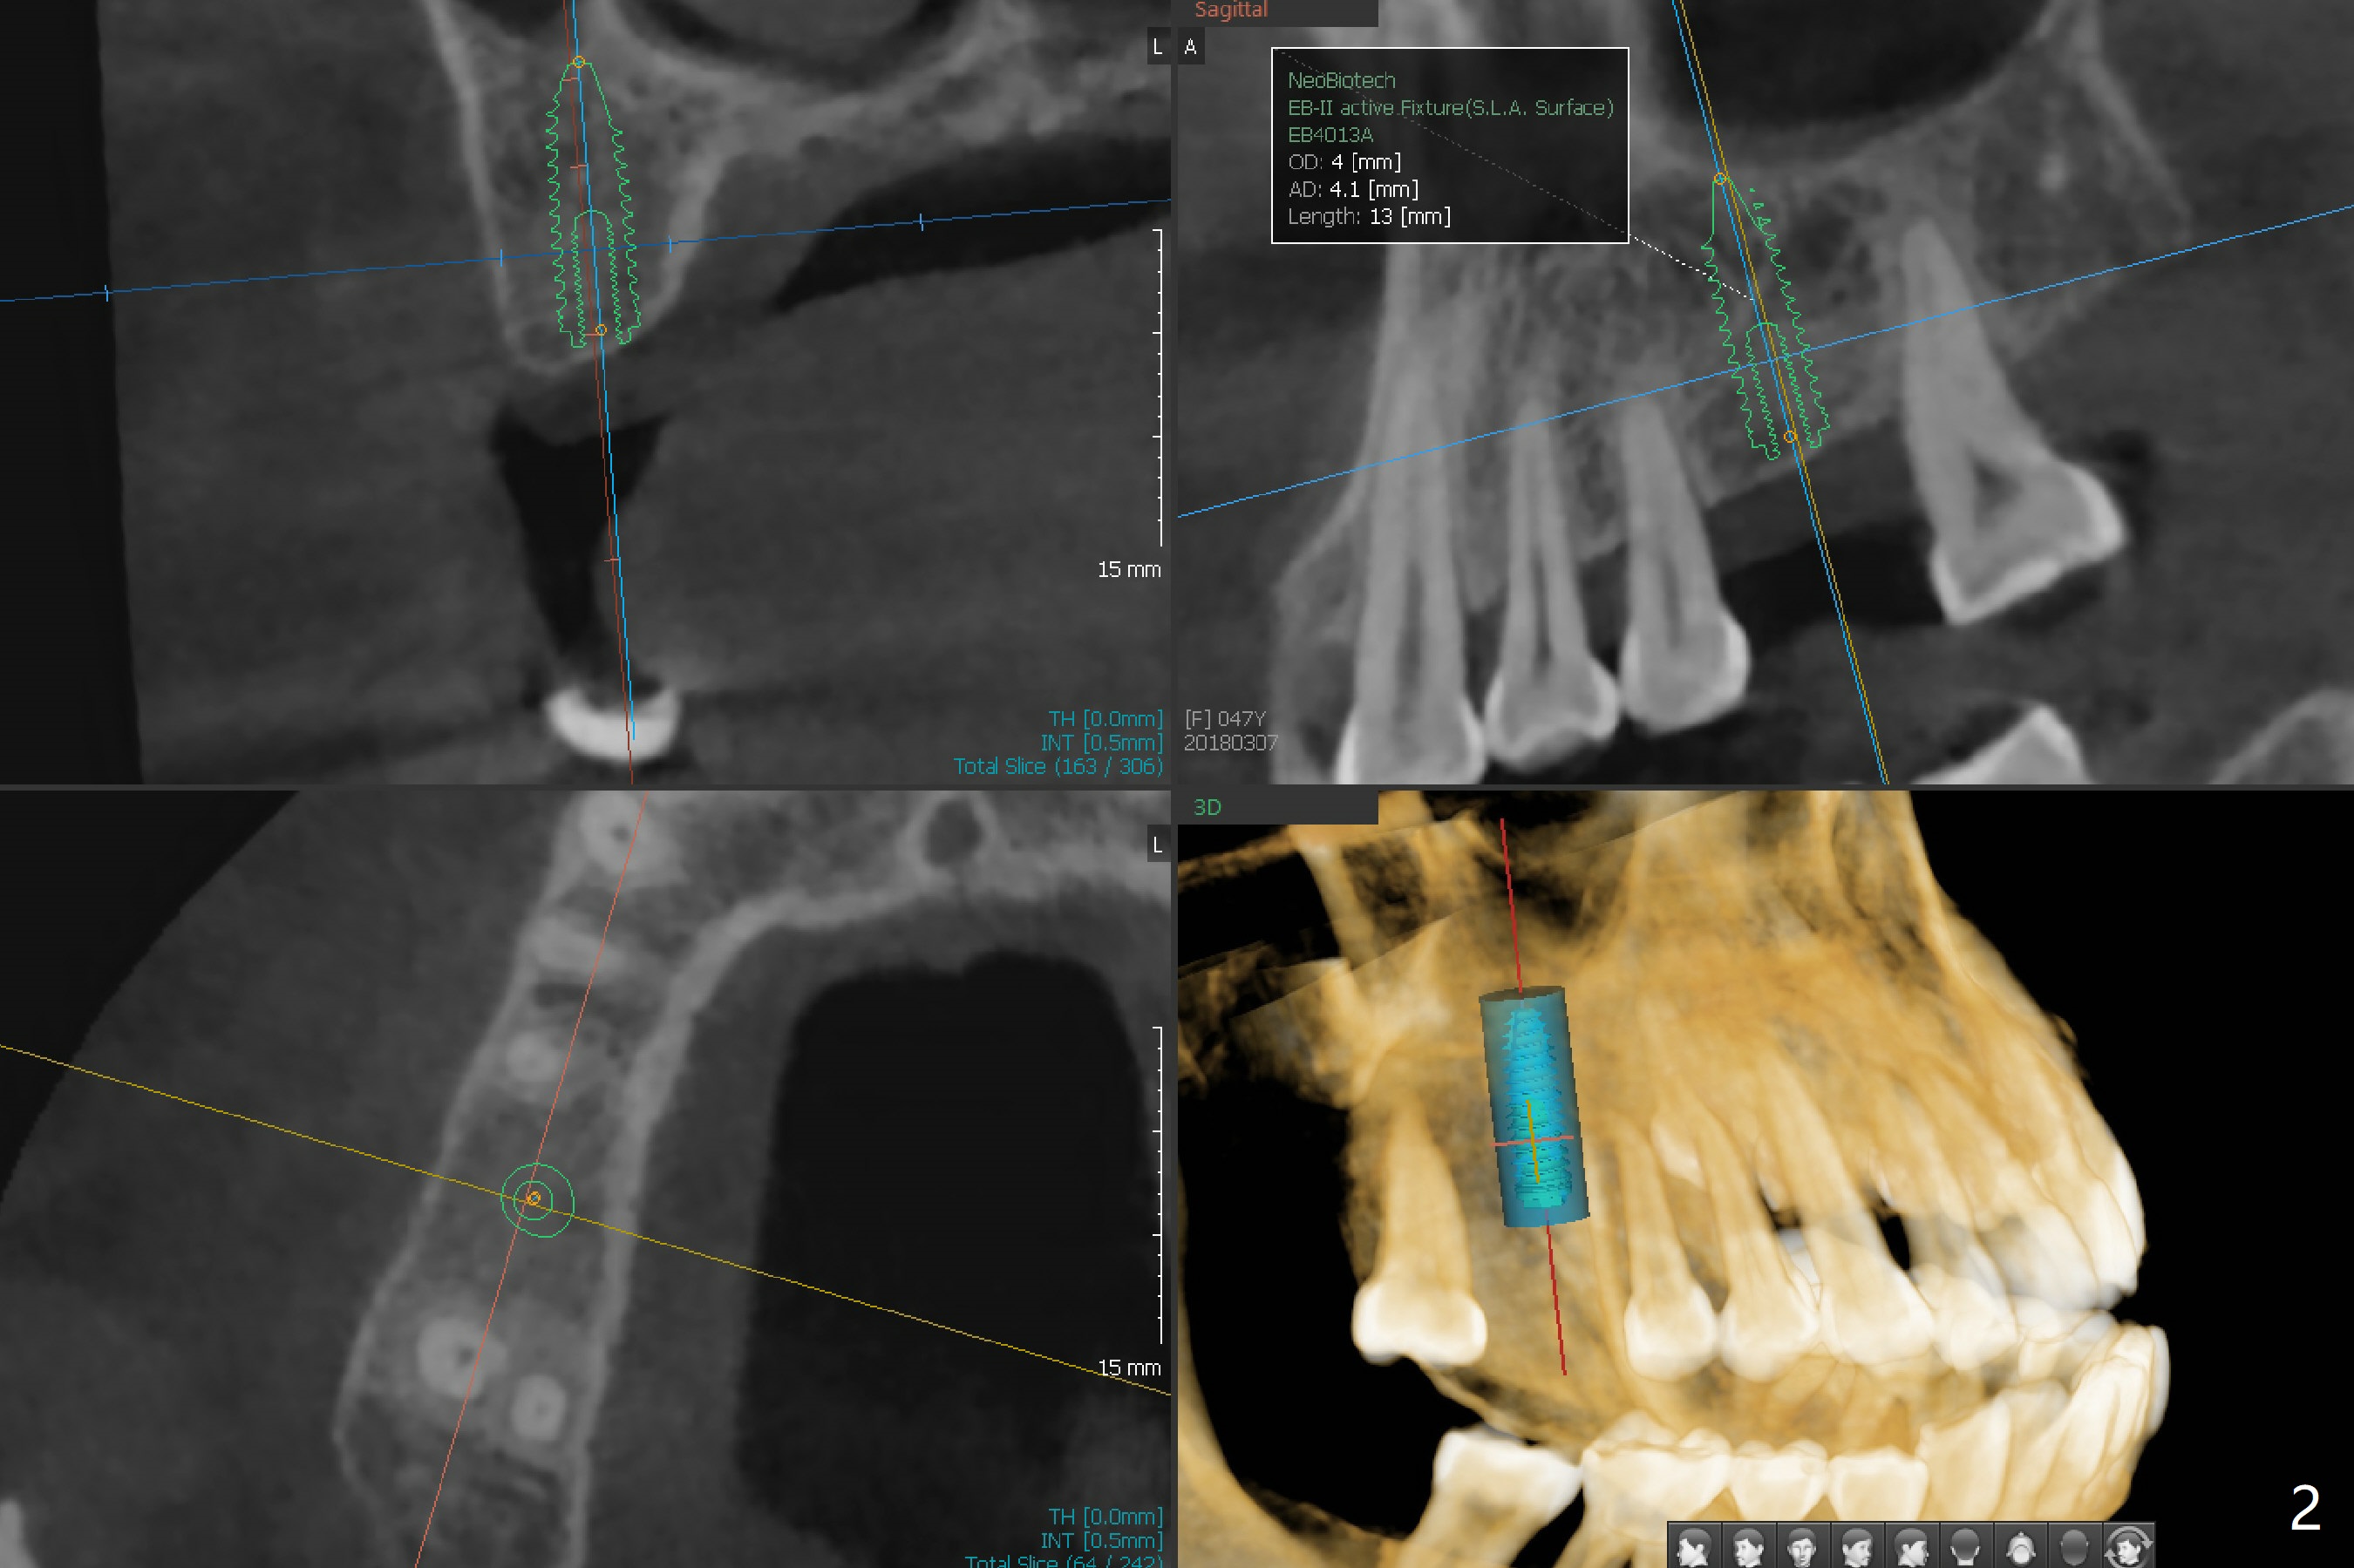

A 47-year-old woman requests implant at #3 (Fig.1). There is generalized bone loss with fair oral hygiene. It suggests bruxism. Night guard will be recommended. The patient appreciates the opportunity of having an implant with guided surgery (Fig.2). In fact the root tip of the upper right 2nd premolar curves distal. A 5x11.5 mm implant placed has limited clearance. The blood supply may be compromised.